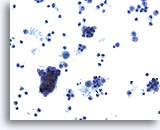

Figure 5

Bronchoalveolar lavage

Oral squamous cells are common in respiratory specimens.

20x

Bronchoalveolar lavage

Oral squamous cells are common in respiratory specimens.

20x